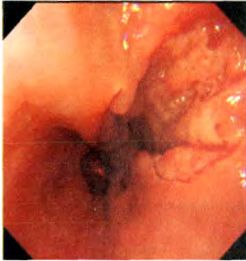

病例资料 患者,男,54岁,因“进食后腹胀伴暖气、返酸1月余,进食哽咽感2周”入院。起病以来,午后发热,在37.5℃~38.5℃之间波动,无腹痛、腹泻、胸闷及胸痛等表现。当地医院就诊,胸部CT平扫未见异常:胃镜提示:食管距中切牙36 cm至贲门齿状线可见一 1.0 cm×2.0 cm溃疡型肿块,表面污秽,呈结节状,活检质脆,易出血,考虑食管癌可能:病理示食管黏膜慢性炎性反应伴少量炎性坏死渗出物。患者至上海某医院就诊,再次行胃镜检查.提示距中切牙35~39 cm,溃疡新生物,病理提示:食管鳞形上皮及炎性肉芽肿组织。近2周来,患者出现进食后哽咽感,以进固体食物时明显。至我院就诊,行胸部增强CT示,食管下段管壁增厚,符合恶性肿瘤改变;胃镜示,食管距中切牙35~39 cm前壁左侧见黏膜隆起,表面高低不平,溃疡形成,质硬,易出血,见图1。超声胃镜示,局部食管壁各层结构消失,考虑食管恶性肿瘤,见图2。但病理示:食管鳞形上皮轻度增生,并见炎性肉芽组织和炎性渗出坏死物,符合炎性溃疡,见图3。遂行肠镜检查.提示回盲部溃疡,肠镜病理示炎性肉芽组织和炎性渗出坏死物,符合炎性溃疡,灶性区似有裂隙性溃疡,符合CD。综合考虑患者病史及各种辅助检查,诊断为:食管CD。

图1 胃镜示食管下纵形溃疡